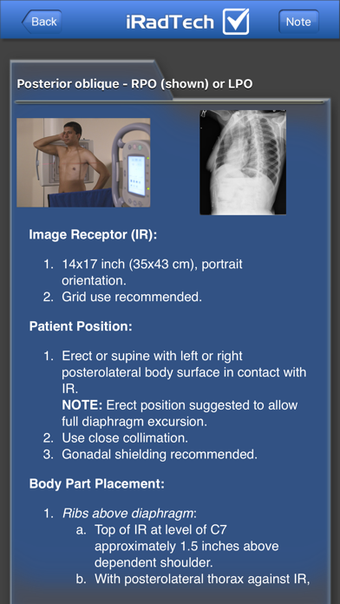

IRadTechهو برنامج إصدار كامل لأجهزة iPhone ، وهو جزء من فئة "الطب" أ>.

حول IRadTech لأجهزة iPhone